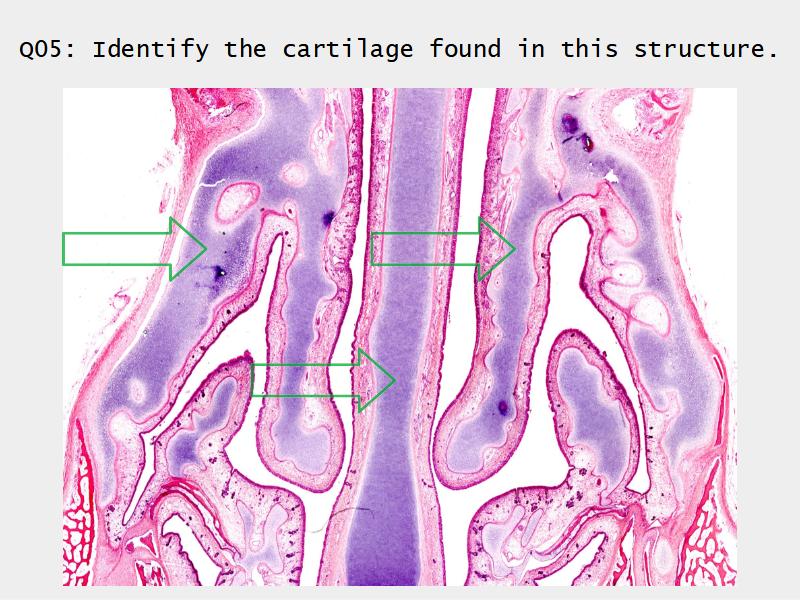

Slides: Respiratory System

- Slide 73: Trachea

Trachea

Bronchi - Transitions

- Intrapulmonary bronchi

- Irregular cartilage

- Respiratory epithelium